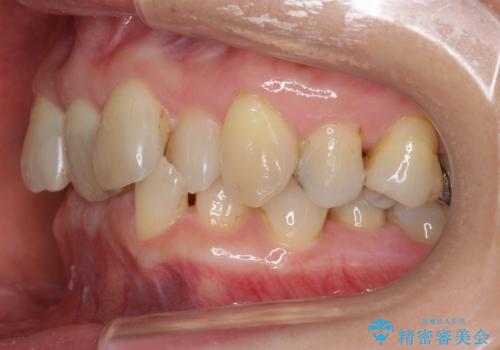

50代女性 インビザライン かみ合わせが深く、難しい症例

かみ合わせが深く、上の歯が咬みこんで下の歯にワイヤーがつけられない状態で、ワイヤー矯正はかなり難しい状態でした。

反対咬合や、すれ違い咬合もあり、大変難しいケースでしたが治療することができました。